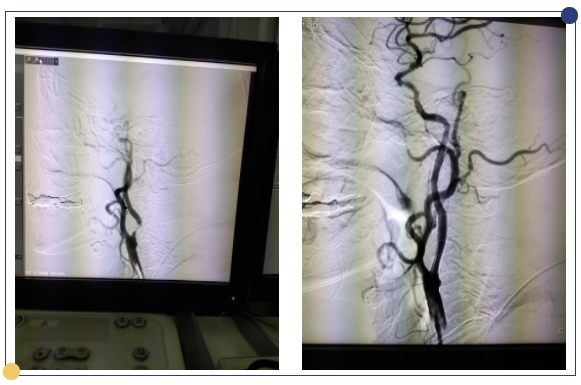

颈动脉狭窄介入术(CAS):是治疗颈动脉狭窄的经典的治疗方式,手术中医生将指引导管到位后,将微导丝小心通过患者颈动脉狭窄病变处,再沿细导丝用不同球囊扩张颈动脉的狭窄区域,然后在后期置入颈动脉的支架来控制这个狭窄的弹性回缩或者夹层,维持持续的血运。一般推荐在整个治疗过程中使用远端的栓子保护装置,就是脑保护伞,这个脑保护伞是在我们导丝、导管通过病变以后,置入到病变的远端,在球囊扩张的过程中和支架置入的过程中,在病变的远端进行血栓的过滤。栓子保护装置的使用大大降低了手术并发症的发生率。